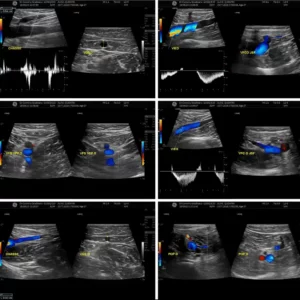

Lire la suiteEcho doppler : examen essentiel avant et après une chirurgie du lipœdème

En effet les symptômes peuvent faire penser à un problème...